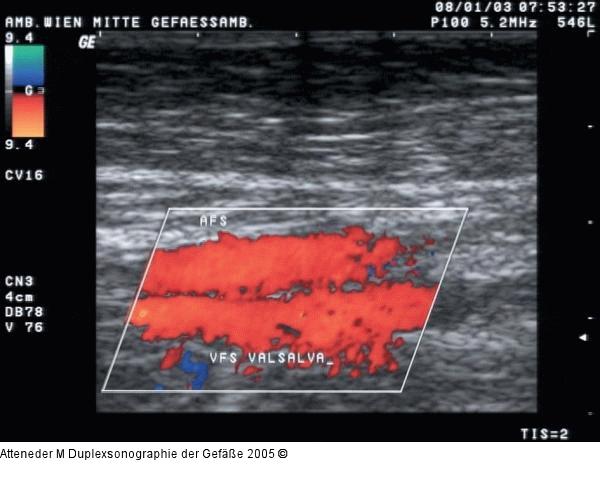

Abbildung 17: Duplexsonographie - Postthrombotisches Syndrom Postthrombotisches Syndrom im Farbdoppler; bei Provokationsmanöver Flußumkehr in der V. fem. sup. und somit gleiche Farbkodierung der Vene wie der begleitenden Arterie |

Postthrombotisches Syndrom im Farbdoppler; bei Provokationsmanöver Flußumkehr in der V. fem. sup. und somit gleiche Farbkodierung der Vene wie der begleitenden Arterie |